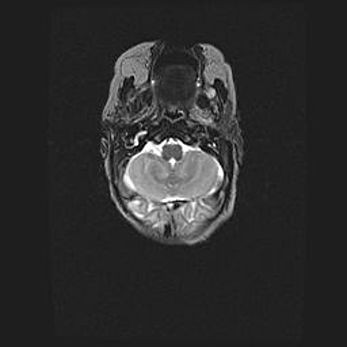

Церебральная ишемия II.

Возраст: 5 дней

Вес: 3400 г

Пол: женский

Окружность головы: 35 см

Срок гестации: 39 недель

Церебральная ишемия – это заболевание, характеризующееся недостаточностью (гипоксией) либо полным прекращением (аноксией) снабжения мозга кислородом по причине закупорки одного или нескольких сосудов. Это приводит к  что метаболическим расстройствам различной степени тяжести в тканях головного мозга, развитию коагуляционных некрозов и гибели нейронов.